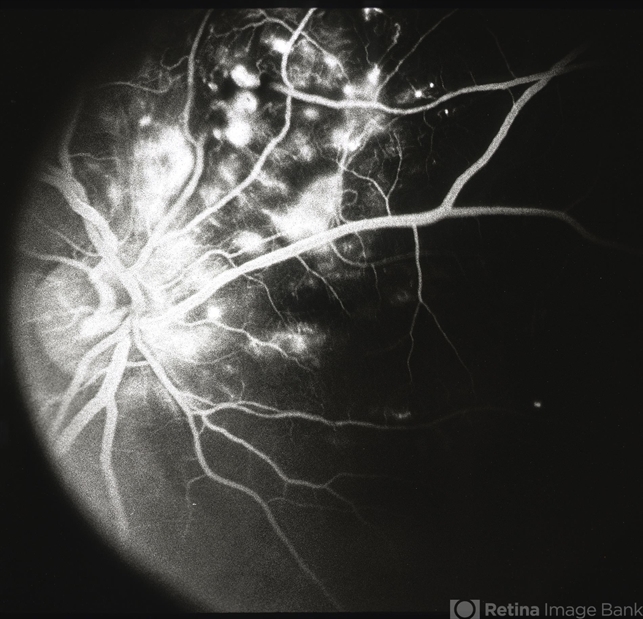

- Coats disease

- congenital retinal telangiectasis

- Flourescein angiogram with leakage of the telangectatic and dilated aneurysmal-like abnormal vessels.